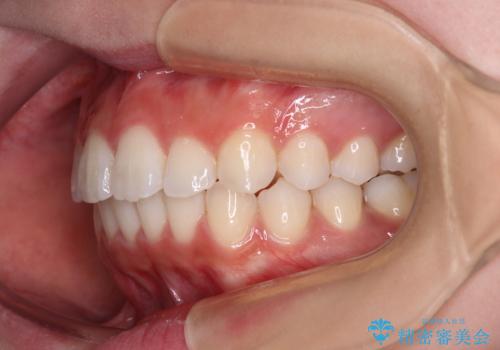

欠損した歯と前に飛び出した前歯 インプラント治療を併用したワイヤー矯正治療

上顎歯列全体を後方移動させたことで唇に当たる感覚は改善され、更には上下の正中位置も合わせることができました。